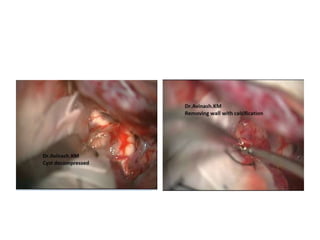

Craniopharyngioma

FIGURE 4. The capsule of the cystic craniopharyngioma was firmly attached to the left

hypothalamus, the stalk was dislocated to the right side (Patient 6). The outgrowth of the

craniopharyngioma from proximal stalk is recognizable A. Complete removal of the capsule was

possible, but produced subpial blood injection over the left hypothalamic surface B. MRI scan

revealed a small ischemic injury in the left hypothalamus C. This patient had transient sleep

disorder, moderate hyperphagia and memory problems (see also a supplemented video

material 1).